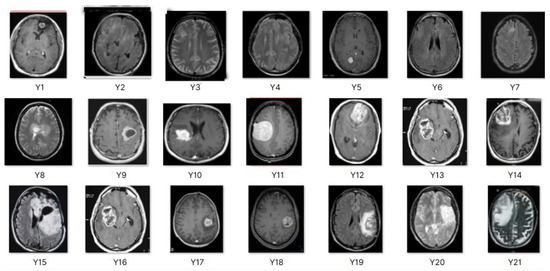

This work collects images from the Kaggle Brain MRI for Brain Tumor Detection dataset, which consists of 253 files with cancer and non-cancer brain images. The sample MRI is illustrated in Figure 2. The dataset has two folders: no tumor encoded as 0 and tumor as 1. The labeled data is more helpful in extracting the patterns from the MRI, which is used to predict the new images related output. The collected image consists of noise information that reduces the performance of brain tumor recognition accuracy. Therefore, image noise should be eliminated to improve the overall prediction efficiency.

Figure 2.

MRI samples Normal Brain MRI (Y1 to Y8) Benign tumor MRI (Y9 to Y15) Malignant tumor MRI (Y16 to Y21).